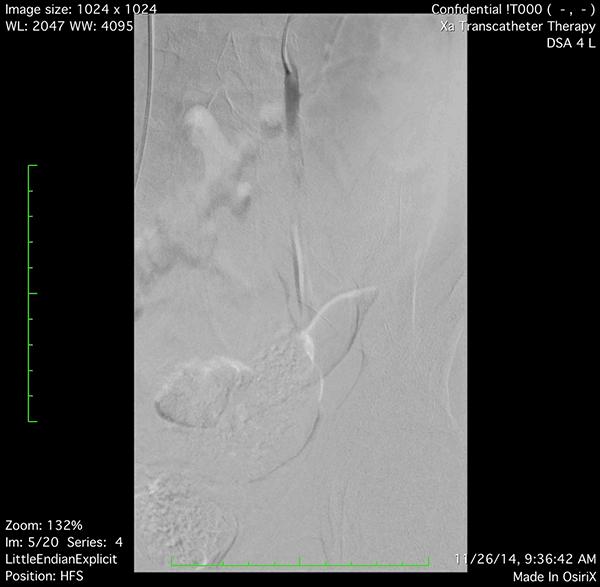

较重的精索静脉曲张、精子数连续三次在2千万以下或有*丸睾**萎缩者;平卧时曲张之静脉可消失者,可通过腹腔镜、显微镜或是开放式,经髂窝腹膜后精索静脉高位结扎术、经腹股沟精索静脉结扎术或紧缩静脉介入栓塞术等进行治疗。